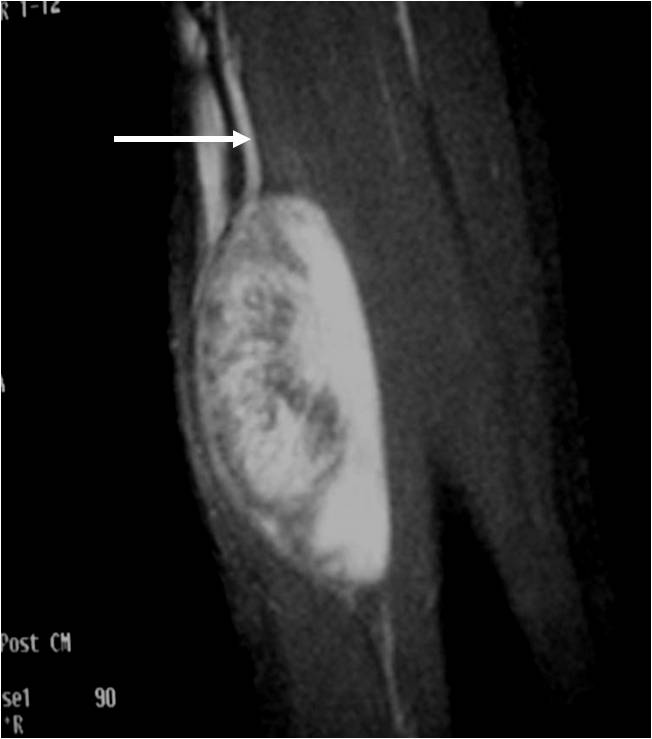

• • The work-up for Schwannoma often consists of a physical examination, X-ray, MRI, CT, and bone scans. The diagnosis is often confirmed with a biopsy, which samples the tumor for further analysis.

Radiographic imaging is used to help form a diagnosis. These include X-Ray, MRI, CT and Bone Scans

An example of an MRI is shown.

Schwannoma MR